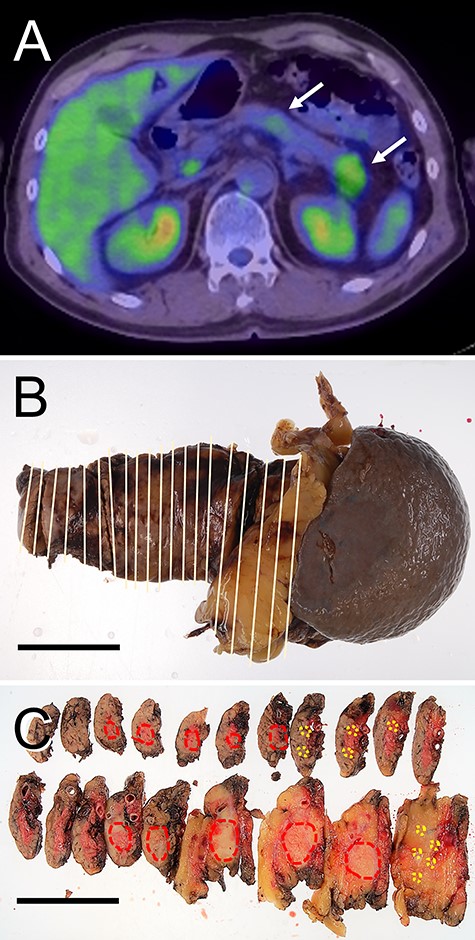

Radiological features and macroscopic findings of Case 3. (A) FDG-PET. (B) Macroscopic finding of the pancreas. (C) A nodular lesion (red circles) and foci small lesions (yellow circles) were indicated on the cut surface.

A nodular mass was noted in the body or tail of the pancreas by USG in three cases (Figs 1–3). Endoscopic ultrasound-guided fine needle aspiration gave negative result in all patients. No lesion was detected by computed tomography (CT) (Fig. 1B and Table 1). Low-intensity mass was detected in the body or tail with T1-weighted imaging of magnetic resonance imaging (MRI: Fig. 1C and Table 1). 18F-fluorodeoxyglucose positron-emission tomography (FDG-PET) detected two lesions with high standardized uptake value (SUV) in the body and tail in Cases 1 and 2 (Figs 1D and2A and Table 1) and one lesion in the body in Case 3 (Fig. 3A and Table 1). In the resected pancreas, two lesions were found in the body and tail of the pancreas in Cases 1 and 2 (Figs 1F and2C, red circles) and one lesion of the pancreatic body in Case 3 (Fig. 3C, red circles). Small foci of lymphoid hyperplasia were noted in all cases (Figs 1F, 2C and3C, yellow circles).